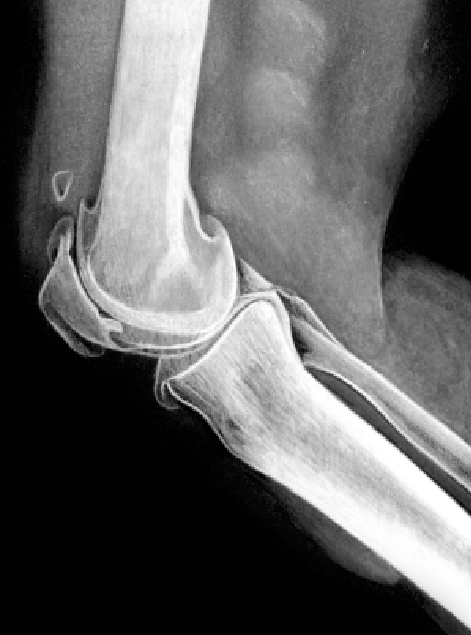

Dolor de rodilla por artrosis:

Descansar y evitar hacer actividades que ocasionen dolor.

Evitar poner peso en la rodilla.

Aplicar hielo y cubrir la rodilla antes de aplicarlo. No dejar el hielo aplicado durante demasiado tiempo ya que podría producir una quemadura por frío.

Mantener la rodilla elevada para reducir la hinchazón.

Usar un vendaje elástico.

Dormir con una almohada por debajo o entre las rodillas.

Bajar de peso si hay sobrepeso u obesidad.

Si se tiene pies planos usar plantillas y soportes de arco.